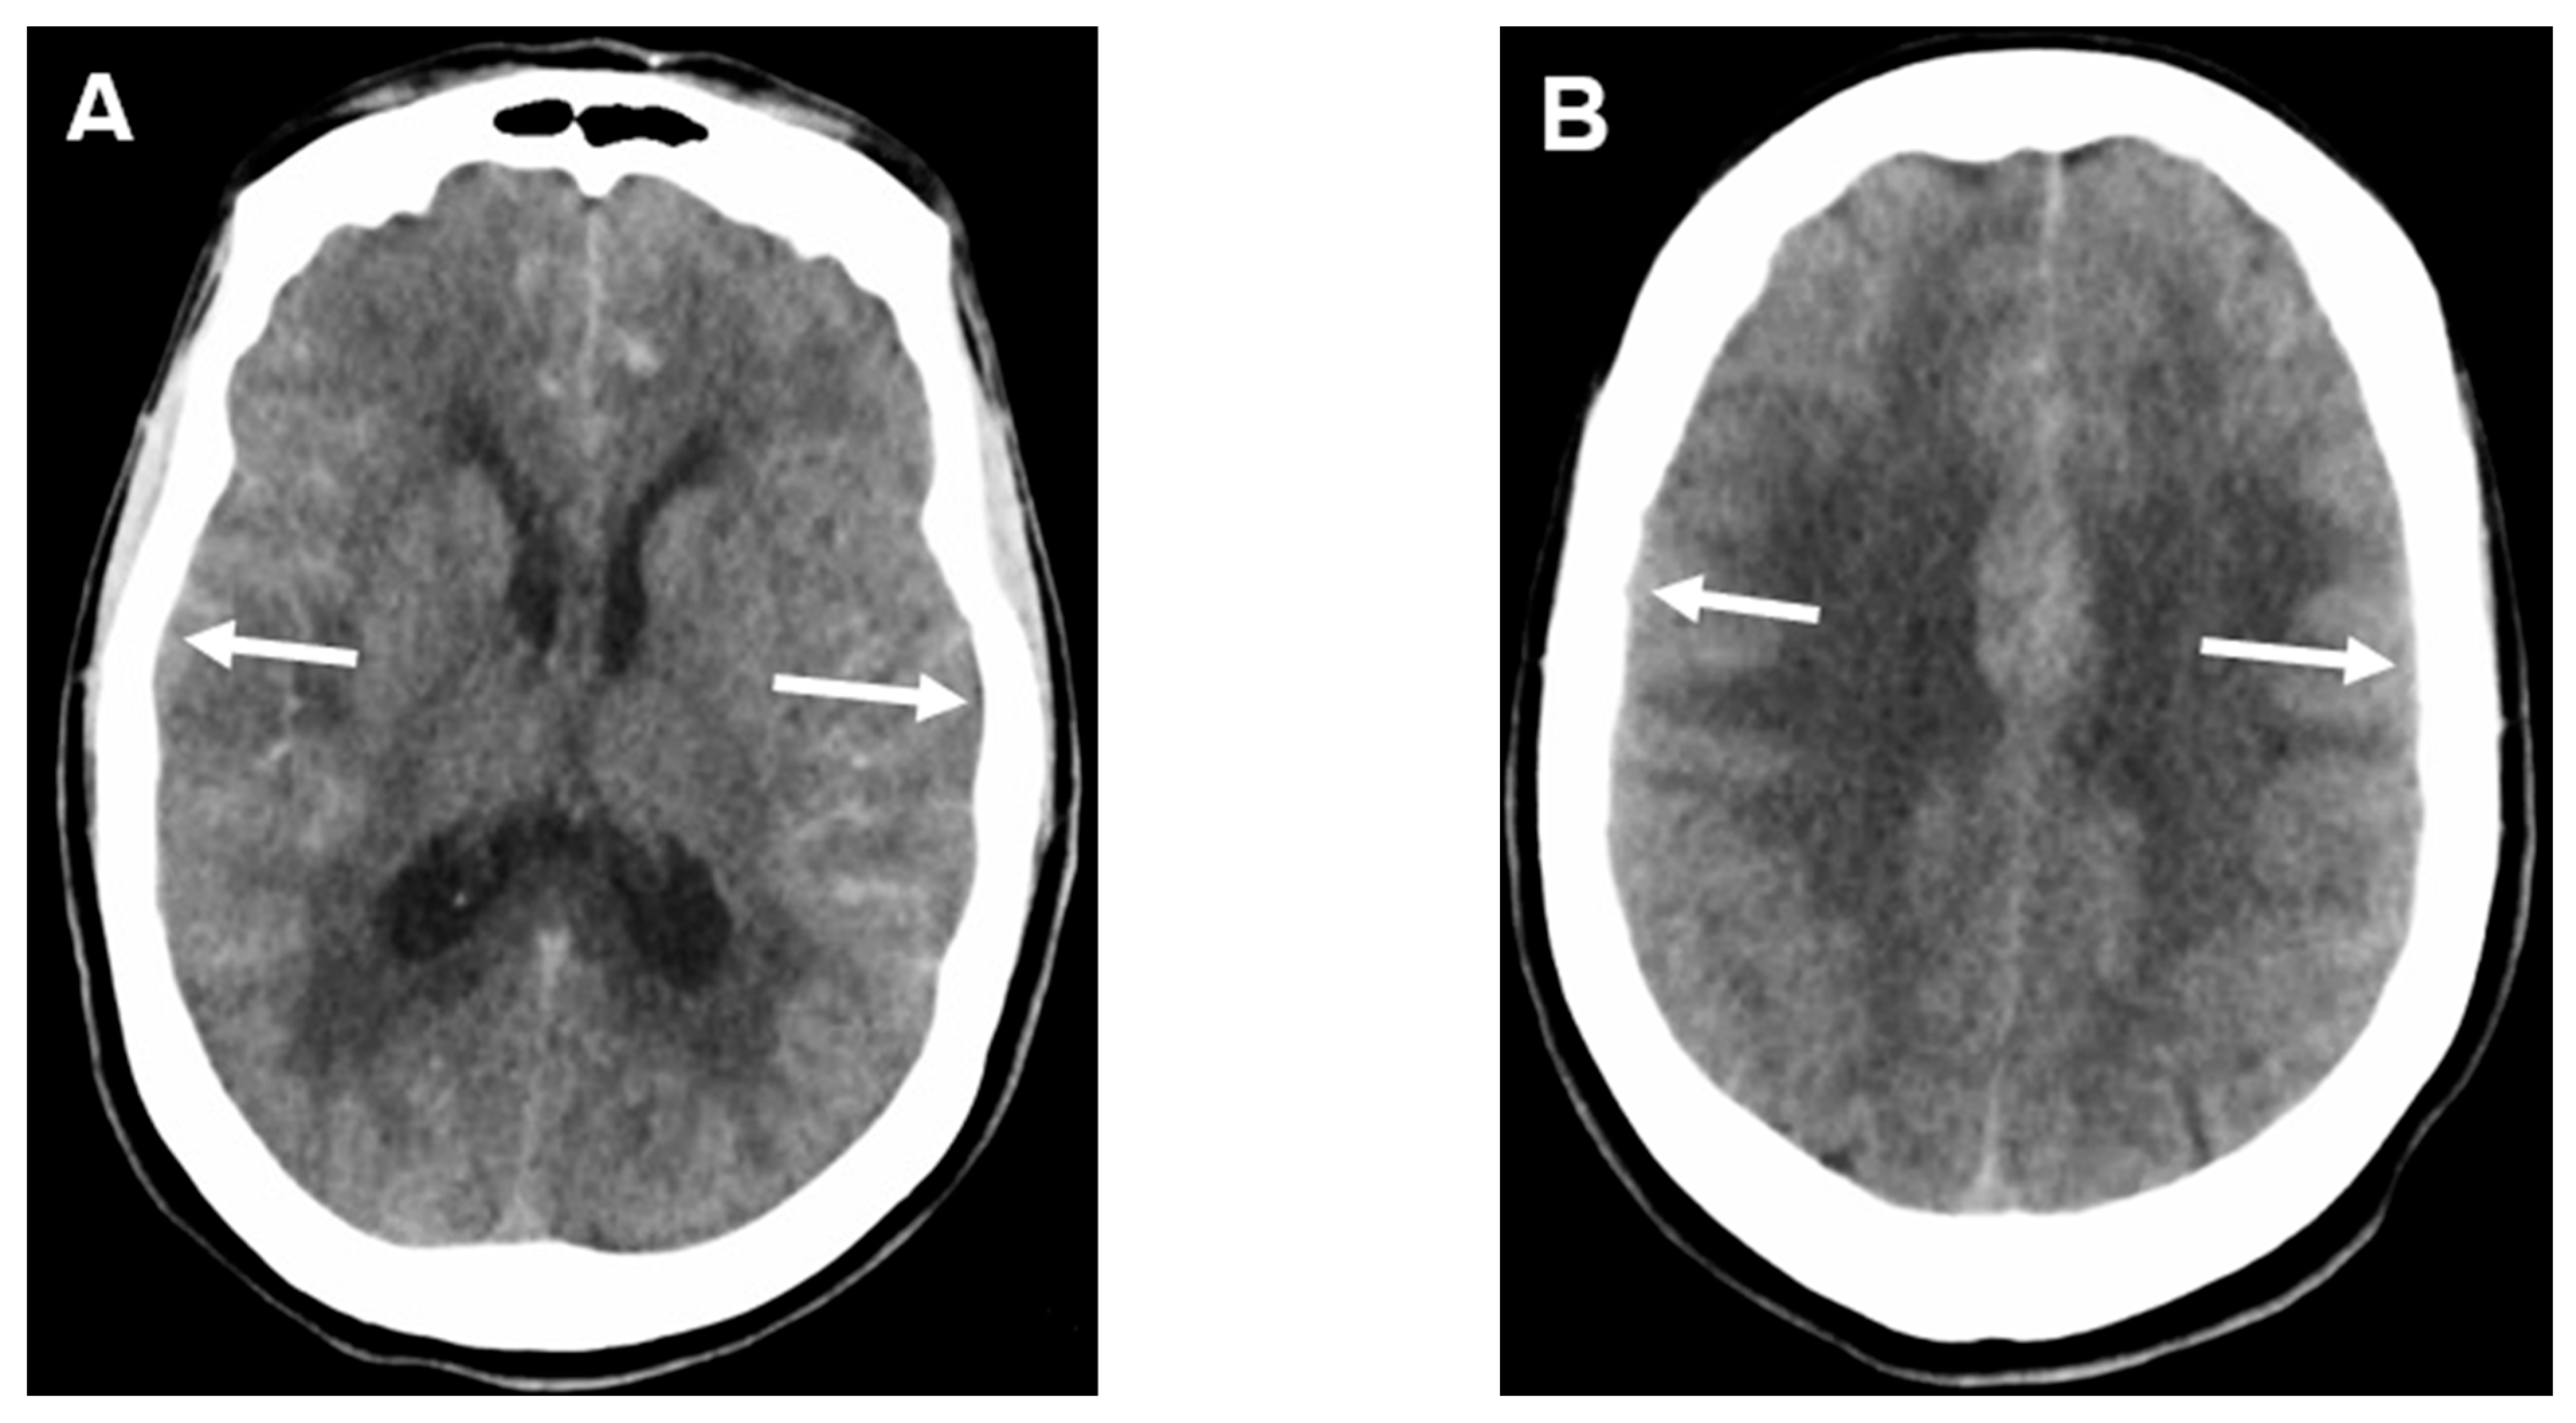

- Ahn, S.H.; Savarraj, J.P.; Pervez, M.; Jones, W.; Park, J.; Jeon, S.B.; Kwon, S.U.; Chang, T.R.; Lee, K.; Kim, D.H.; et al. The Subarachnoid Hemorrhage Early Brain Edema Score Predicts Delayed Cerebral Ischemia and Clinical Outcomes. Neurosurgery 2018, 83, 137–145. [Google Scholar] [CrossRef]

- Said, M.; Gumus, M.; Herten, A.; Dinger, T.F.; Chihi, M.; Darkwah Oppong, M.; Deuschl, C.; Wrede, K.H.; Kleinschnitz, C.; Sure, U.; et al. Subarachnoid Hemorrhage Early Brain Edema Score (SEBES) as a radiographic marker of clinically relevant intracranial hypertension and unfavorable outcome after subarachnoid hemorrhage. Eur. J. Neurol. 2021, 28, 4051–4059. [Google Scholar] [CrossRef] [PubMed]